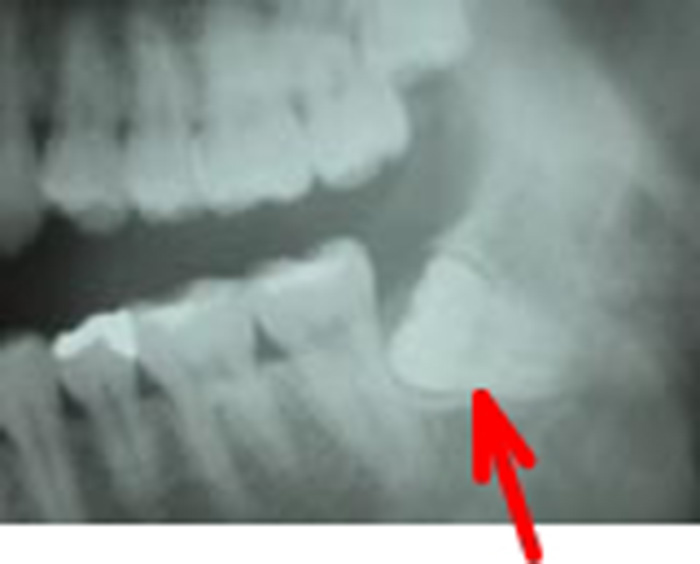

当科では、術前に歯科用3次元CTを用いて正確な診断を行い、炎症がある場合は抗生剤を用いて消炎後、抜歯を行っています。埋伏智歯の場合、歯肉粘膜の切開、骨の削除、智歯の分割、創部の縫合を必要とします。

左側下顎水平埋伏智歯